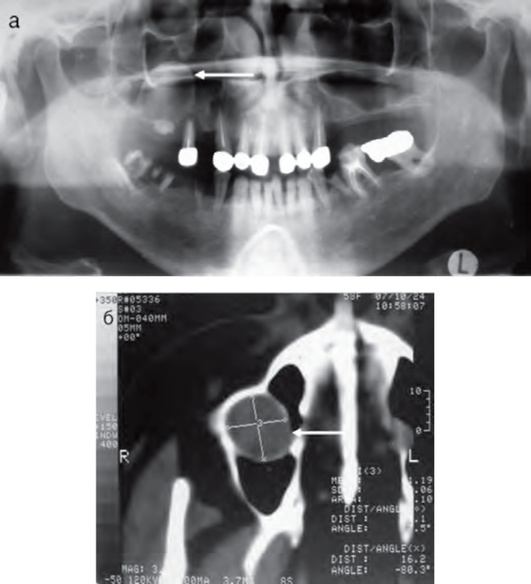

Форум верхнечелюстная киста

Форум верхнечелюстная киста 108 фото